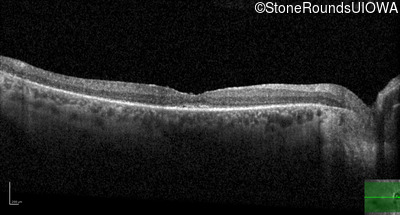

Age at visit:

31 years

OD

OS

20/50 -2

20/50

AR Retinitis Pigmentosa

ZNF408

His455Tyr CAT>TAT

Arg567Stop CGA>TGA

AR